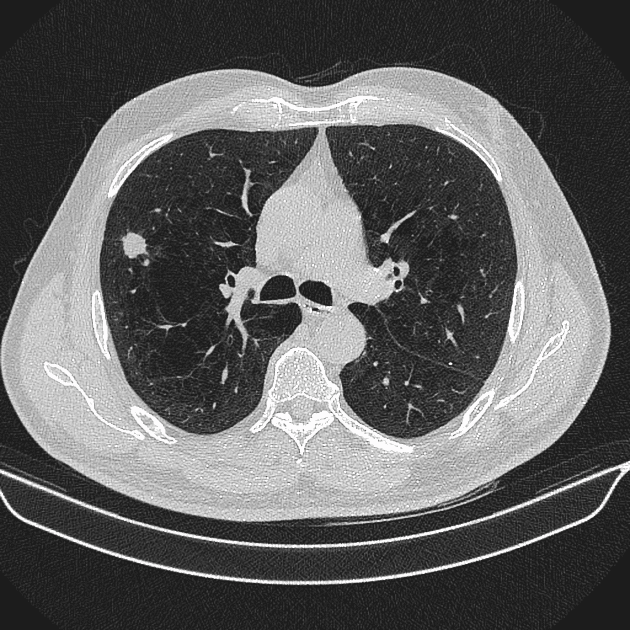

U phổi

» Thông tin: Nam giới – 70 tuổi.

» Lâm sàng: Ho / Tiền sử hút thuốc lá.

# Ung thư biểu mô tuyến (Adenocarcinoma).